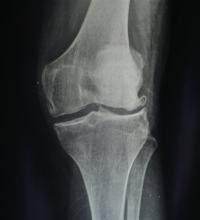

膝關節退行性關節炎好發於負重較大的膝關節,幾乎所有病例都有不同程度的疼痛,隨病程緩慢進展。主要表現膝關節開始活動時疼痛明顯,稍活動後疼痛減輕,然而負重和膝關節活動過多時,疼痛又會加重,這是骨關節病的特點。有時疼痛可呈放射性,如髖關節疼痛可放射至大腿內側,膝關節附近。早期可見關節僵硬,如膝關節長時間處於某一體位時,自覺活動不利,起動困難,後逐漸出現關節不穩,關節屈伸活動範圍減少及步行能力下降,尤以上下台階,下蹲,跑,跳等能力下降更加明顯。有些膝關節病晚期病人還可能出現一些下肢畸形,以膝內翻最常見,即俗稱的“羅圈腿”。症狀

膝關節疼痛是膝關節退行性關節炎的主要症狀,表現為鈍痛,晨起或關節處於某一位置過久後,疼痛最為明顯,稍加活動即可減輕。但活動過多時,由於膝關節摩擦又感疼痛,氣候變化時疼痛加重。患者感到膝關節不靈活,休息後更覺明顯。膝關節出現僵硬狀態,活動時膝關節可發出粗糙的摩擦聲。這些症狀可隨著病理變化的加劇而加重。除疼痛外,局部地區腫脹、有滲液,肌肉萎縮,甚至出現關節畸形,活動受限。治療